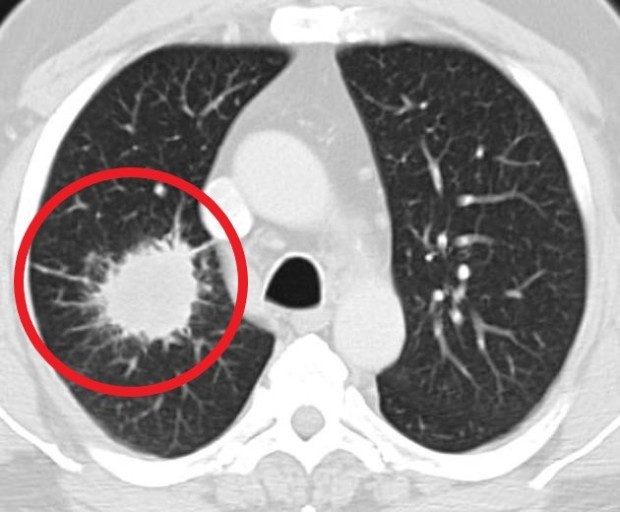

폐렴 증상 폐렴은 폐의 세균, 바이러스, 곰팡이 등 감염으로 인해

폐포(폐 속의 공기 주머니)에 염증이 생기고, 고름이나 액체가 차는 질환입니다.